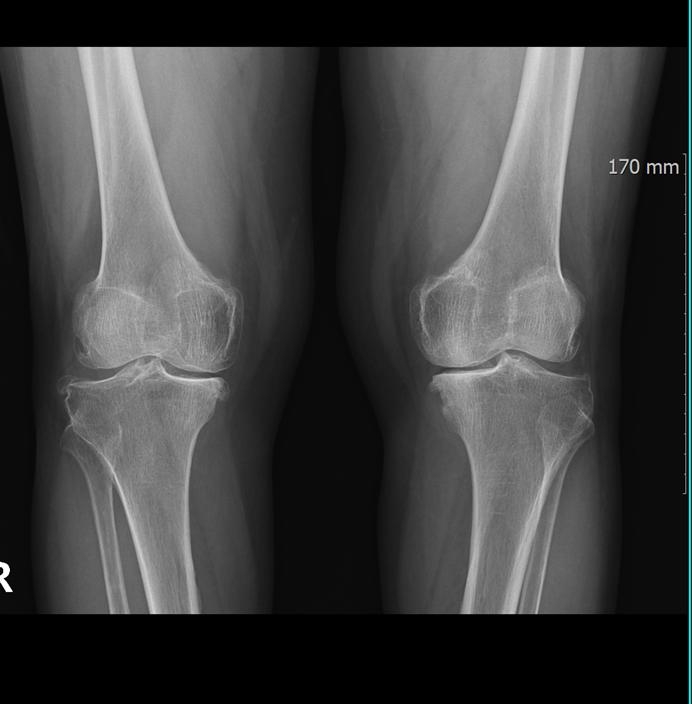

Overcoming Knee Pain with Exercise? The Hidden Trap of Overuse